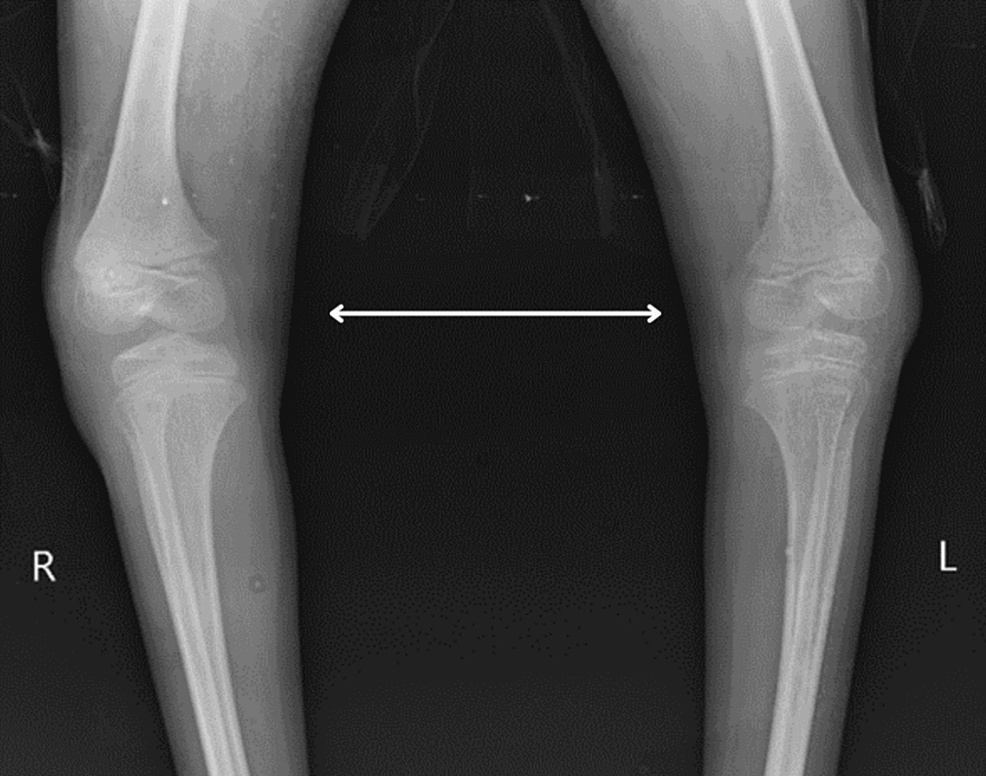

Preschooler with talipes equinovarus of the left foot Pediatric Talipes Equinovarus Angle Radiology Web congenital talipes equinovarus is considered the most common anomaly affecting the feet diagnosed on antenatal ultrasound. Web congenital talipes equinovarus (clubfoot) is one of the most common congenital malformations; The purpose of this article is to discuss the radiographic assessment of pediatric foot alignment. Abnormalities discussed include, but are not limited. Web lateral view in talipes equinovarus demonstrates an. Talipes Equinovarus Angle Radiology.

Talipes Equinovarus Angle Radiology . Web congenital talipes equinovarus (ctev), also known as clubfoot, is a common musculoskeletal entity that affects one to. Web clinical scenarios are included to orient the learner to the evaluation of pediatric foot alignment. Web clubfoot, also known as congenital talipes equinovarus, is a common idiopathic deformity of the foot that presents in neonates. Web lateral view in talipes equinovarus demonstrates an abnormally elevated tibiocalcaneal angle. The purpose of this article is to discuss the radiographic assessment of pediatric foot alignment. Web congenital talipes equinovarus is considered the most common anomaly affecting the feet diagnosed on antenatal ultrasound. Web congenital talipes equinovarus (clubfoot) is one of the most common congenital malformations; Abnormalities discussed include, but are not limited.